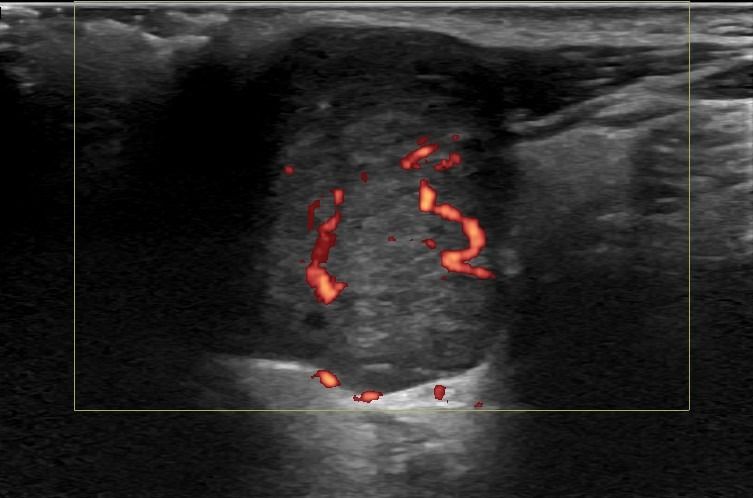

- Εστιακές βλάβες, όπως όγκοι (πλειόμορφο αδένωμα, όγκος Warthin, λέμφωμα)

Η αξιοπιστία του Υπερηχογραφήματος στη διάγνωση παθολογίας των Σιελογόνων Αδένων έχει καθιερωθεί τα τελευταία χρόνια και εξασφαλίζεται με τη χρήση Υπερηχογράφων τελευταίας γενιάς με ειδικούς υψίσυχνους ηχοβολείς και με την εξοικείωση και εμπειρία του εξεταστή-ιατρού με την ηχοανατομία και παθολογία των Σιελογόνων Αδένων και της περιοχής κεφαλής – τραχήλου.